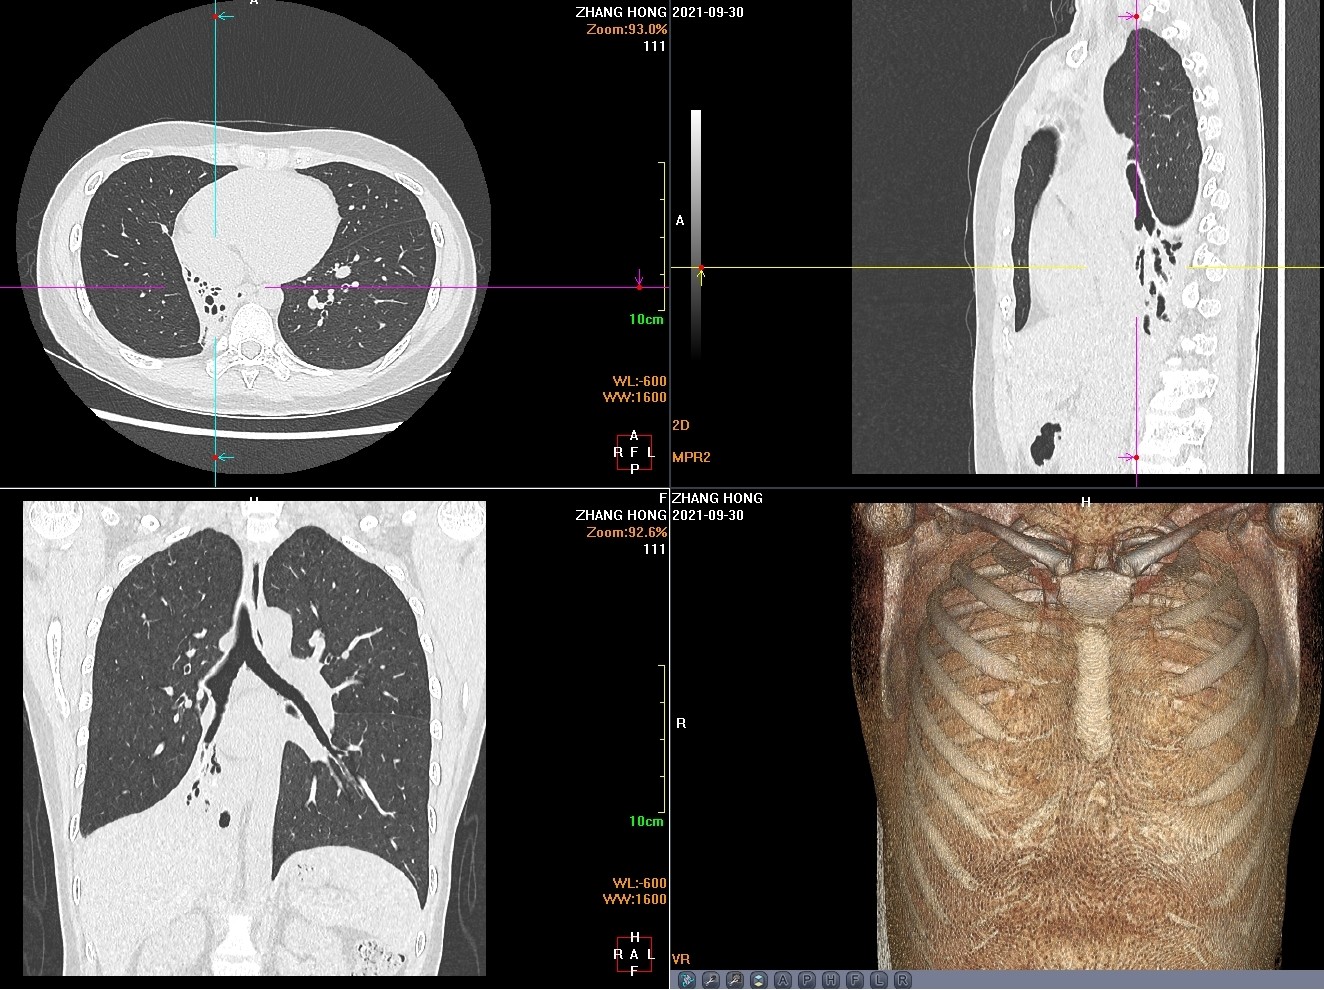

患者2年前无明显诱因出现咳嗽,偶有少量黄色痰液,无发热,无盗汗,无咯血,无胸闷、胸痛,就诊于我院肺科,痰结核菌涂片提示阳性,胸部CT提示右肺下叶感染性改变,考虑继发性肺结核伴支气管扩张,予抗结核治疗1年后遵医嘱停药。患者仍间断咳嗽,咳脓痰,反复发作,间断加重,严重影响生活,为进一步治疗,就诊于我院胸外科门诊,复查胸部CT提示右肺中叶及下叶萎陷不张,不张肺组织内支气管扩张及散在钙化灶。以“,继发性肺结核,右侧毁损肺”收入院。下图是患者胸部CT,显示右肺中下叶肺毁损。

入院后完善检查,未见明显手术禁忌症,于2021年10月12日在气管插管全身麻醉下行但操作孔胸腔镜右中下肺叶切除术,术中见右肺中下叶不张实变,肺组织内多发结节样病灶伴钙化。肺门及纵隔见碳末沉着淋巴结,右下肺与胸壁之间可见条索状及膜状粘连,未见胸腔积液,右上肺代偿性膨胀。在完全胸腔镜操作下行右肺中下肺叶切除术,肋间神经及椎旁神经阻滞止疼,手术操作时间126分钟,术中出血20ml,术后患者疼痛轻微,无呕吐恶性等不良反应,术后胸腔引流量少,肺膨胀好,术后第2天拔除胸腔引流管,康复出院。术后2周复查,患者恢复良好,无咳嗽咳痰,无胸痛,无胸闷及气短不适,恢复正常生活。下图是手术后10天胸壁手术切口和切除的右中下肺组织。